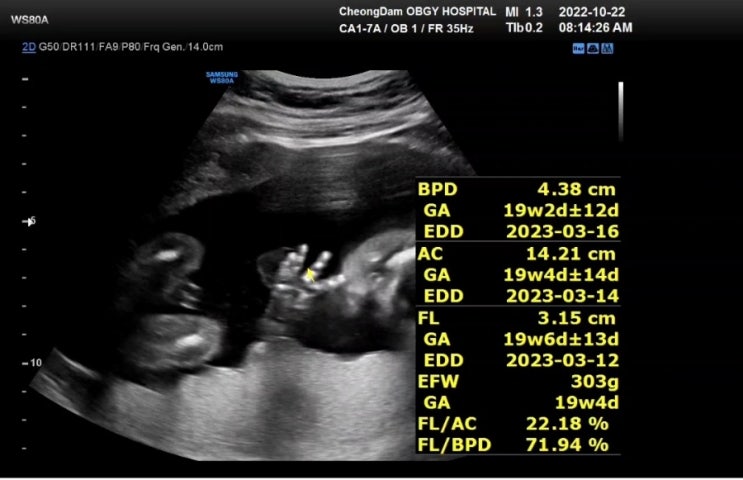

23주 1일차 (11/12. 토) 서울성모병원 두 번째 입원 - 첫째 날 청담마리산부인과에서 서울성모병원으로 전...